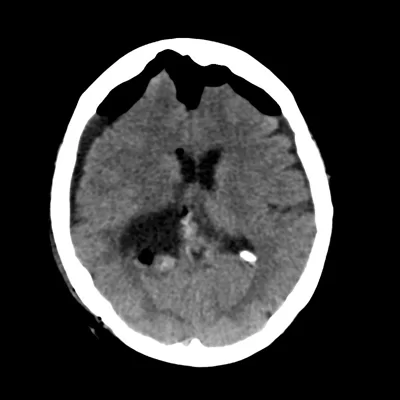

Το 90% των μηνιγγιωμάτων εμφανίζονται εντός του κρανίου, σε διάφορες θέσεις τόσο στην κυρτότητα όσο και στη βάση του κρανίου. Μερικές φορές εμφανίζονται σε σπάνιες θέσεις, όπως για παράδειγμα εντός του σπονδυλικού καναλιού, εντός των κοιλιών του εγκεφάλου (Εικόνα 1) ή στο οπτικό νεύρο.

Η διάγνωση συνήθως τίθεται με τον νευροαπεικονιστικό έλεγχο, δηλαδή με την μαγνητική και αξονική τομογραφία εγκεφάλου. Ανάλογα με την εντόπιση, ενδεχομένως να χρειαστούν πιο εξειδικευμένες εξετάσεις όπως πχ. οφθαλμολογική εκτίμηση για έναν όγκο κοντά στο οπτικό νεύρο.